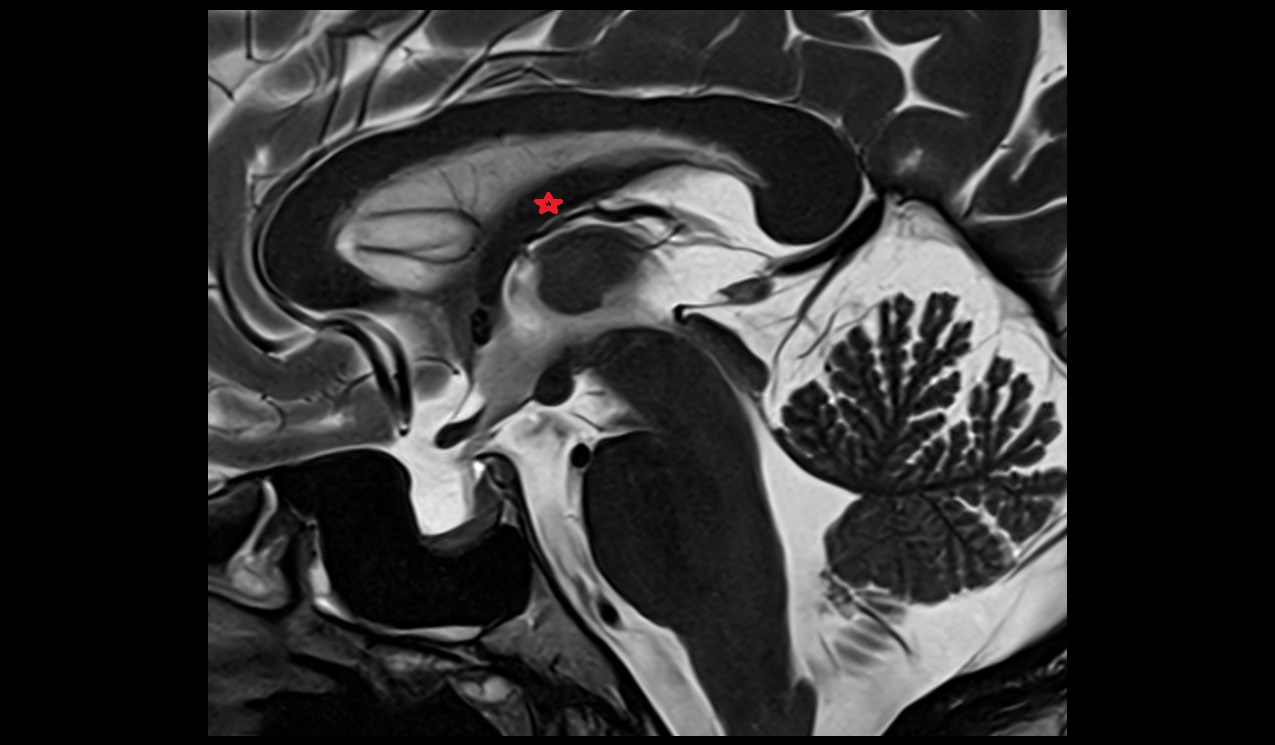

- Uterus (pregnancy)

- Cervix in Pregnancy

- Vagina in Pregnancy

- Fundus of uterus in pregnancy

- Fetal brain

- Fetal cerebellum